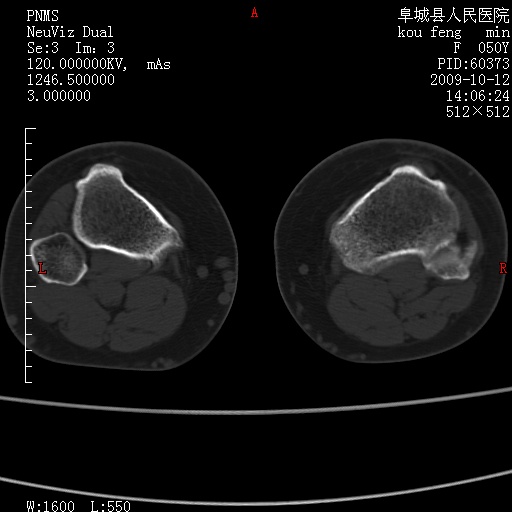

女性,50岁。【请提供患者临床症状体征】

右膝关节退行性改变,关节游离鼠。

右膝关节退行性改变,滑膜黏液囊钙/骨化并游离。

右膝关节退行性改变